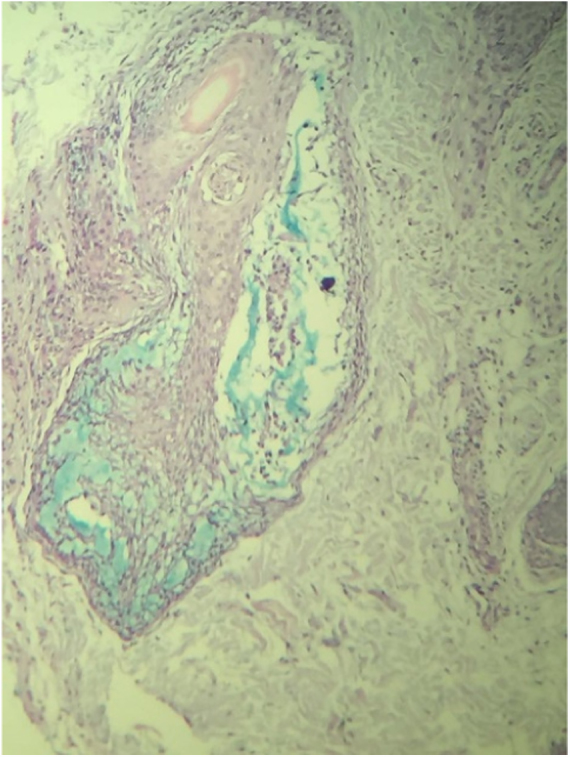

A routine anatomopathological examination (Hematoxylin & eosin staining) reveals preserved epidermis. Dermis presents some hair follicles containing fibromyxoid stroma and mixed pattern inflammatory cells (Fig. 2). Alcian Blue stain reveals built-up mucin in the outer root sheath of the hair follicle (Fig. 3).

Figure 3.

Mucin in the outer root sheath of the hair follicle (Alcian Blue, ×100).

Histopathology is essential for diagnosis since it shows mucin deposits on the outer root sheath of the hair follicle, in addition to inflammatory infiltrates composed of lymphocytes, macrophages and eosinophils with folliculotropic lymphocytes. The benign form is determined by the extension of the eosinophilic inflammatory infiltrate and significant mucinous alterations in the follicular epithelium.5 Similar findings were observed in the patient‘s results. Presence of epidermotropic lymphocytes and dense perifollicular infiltrate of atypical cells suggest a malignant form of the condition; however, no evidence of it was found in the studied patient.